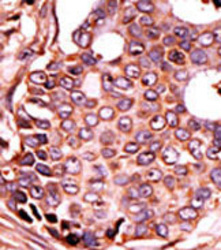

Supportive validation

- Submitted by

- OriGene (provider)

- Main image

- Experimental details

- Formalin-fixed and paraffin-embedded human cancer tissue (breast carcinoma) reacted with the primary antibody, which was peroxidase-conjugated to the secondary antibody, followed by DAB staining. This data demonstrates the use of this antibody for immunohistochemistry; clinical relevance has not been evaluated.

- Validation comment

- IHC